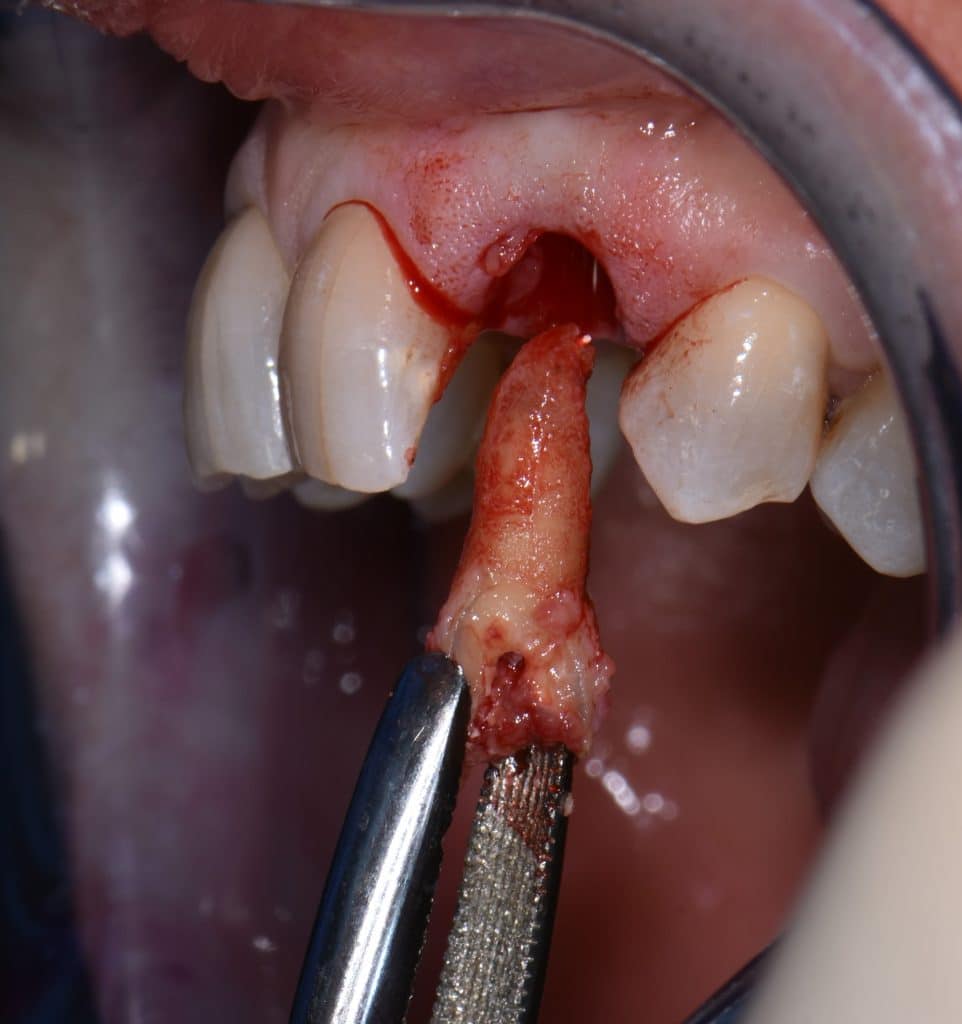

La pz N.G. di anni 52 (ASA 1) viene visitata nel mese di settembre 2017 per la mobilità ed inestetismo dell’elemento protesico 22, (foto iniziali sequenza 1) si evidenzia una frattura parziale della radice, si decide per l’estrazione ( foto sequenza 2) e sostituzione dell’elemento con un restauro implanto-protesico. Purtroppo la scarsa quota ossea apicale all’alveolo post-estrattivo (foto 2 rx) e l’alta valenza estetica dell’elemento ci rende cauti e si programma una socket preservation post estrattiva con l’ausilio delle membrane di prf (foto prf e socket sequenza 3 e 4). Durente i 5 mesi di guarigione la pz porta una protesi parziale mobile (foto 5,2) , a guarigione del sito post estrattivo si evidenzia una buona conservazione dei volumi osseo-gengivali,(foto guarigione sequenza 6) se pur presente una recessione distale all’elemnto 21.Nel mese di febbraio 2018 si procede all’inserimento di un impianto max-stability 3,75x12mm disegnando un lembo anticipato palatino per consentire un aumento dei tessuti vestibolari suturando con tecnica rool flap e trasformando l’elemento parziale mobile in una corona singola a carico immediato sul moncone temporameo applicando i concetti protesici bopt , (foto impianto moncone protesi provvisoria sequenza foto 7-8-9). Durante il periodo di maturazione dei tessuti molli vengono apportate opportune modifiche ai profili del provvisorio al fine di dare maggior spazio al tessuto gengivale, ( fotosequenza 10).Dopo circa 2 mesi dal protesizzazione provvisoria si è proceduto alla realizzazione del manufatto protesico con tecnica chair side sirona con l’ausilio del t-base (foto sequenza 11-12-13), realizzando in una sola seduta una corona in disilicato, ottenendo un risultato più che soddisfacente (Foto 14). Nel controllo a 3 mesi dal carico definitivo si apprezza la perfetta conservazione dei livelli ossei e gengivali. (foto sequenza 15).concludo con un follow up a 18 . Tengo a sottolineare che un caso come questo è stato conducibile con buoni risultati solo grazie alla piena fiducia della pz e alla sua massima motivazione e collaborazione. Ad oggi la pz sorride soddisfatta del risultato. E questo rappresenta la massima ricompensa di chi dedica tutto se stesso alla professione.